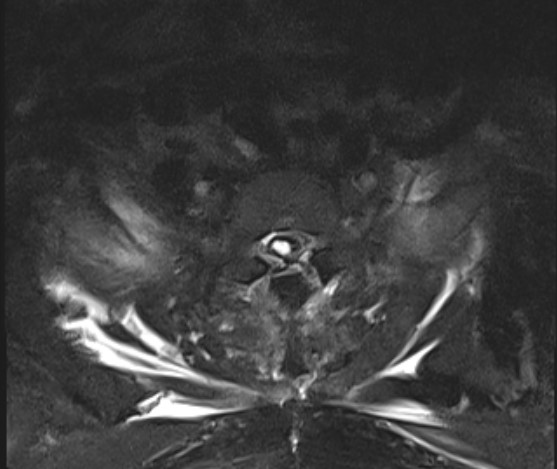

入院核磁共振检查提示T1海绵状血管瘤